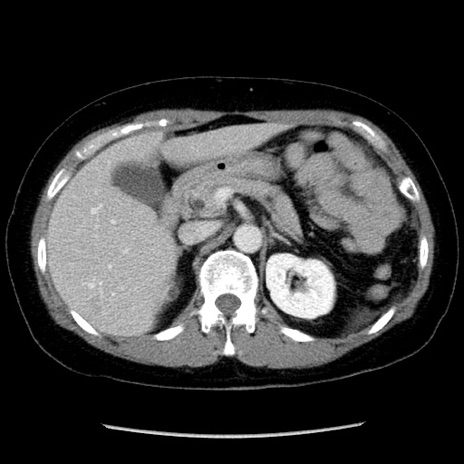

症例6(横断像)

【症例】50歳代女性

【主訴】下腹部痛

【現病歴】本日朝より下痢2回あり。 昼食を食べた後、嘔吐3回、下腹部痛認め、症状軽快せず、当院救急搬送。

【既往歴】卵巣癌術後(8年前に当院で卵巣摘出)

【身体所見】 意識清明、腹部:平坦、腸蠕動音→、やや硬、下腹部自発痛・圧痛あり、反跳痛あり、筋性防御なし。

【データ】WBC 16000、CRP 0.01